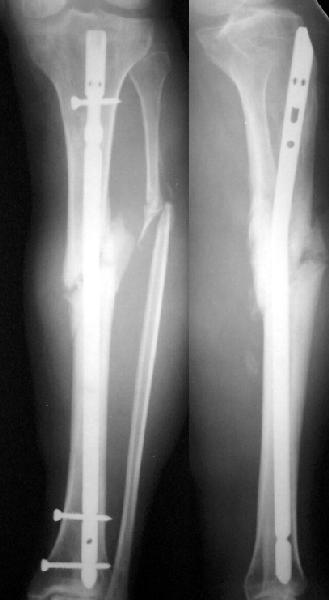

No hollow reamers and nails are still availble yet, so UTN 10 mm was used. After perQ osteotomy of the fibula i tried to open the canal, and the awl was passed to the distal fragment only after closed mobilization of the site to make some antecurvation. It resulted with some anterior translation of the distal fragment :( After impaction the nail was locked dynamically. Images attached. Comments/critics are

welcome.

get_image.jpg

16KB (17241 bytes)

I believe this nailed nonunion of the tibia shaft will likely go on to uneventful healing. Good job.

I'm not clear if you opened the fracture site and used an awl or if you used an awl through the nail entry site. The latter is preferred although often difficult and sometimes impossible.

TAD> I believe this nailed nonunion of the tibia shaft will likely go on to uneventful

TAD> healing. Good job.

Today the case was criticized at the week clinical report for the antecurvation deformity... Unhappily our vice-director tries to prove that such a malalignment is of great clinical importance.

TAD> I'm not clear if you opened the fracture site and used an awl or

TAD> if you used an awl through the nail entry site. The latter is

Yes, nailing was closed, the canal was opened through the nail entry site.

I would expect the deformity of the case of nailed tibia shaft nonunion (slight apex posterior and slight posterior translation) to be of no definite and small theoretical clinical importance.